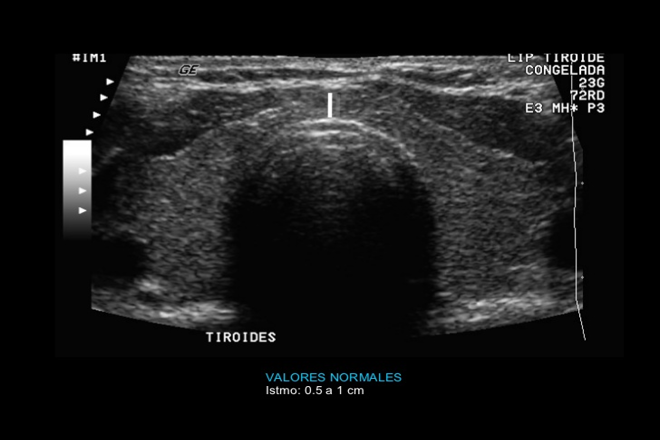

La ultrasonografía es una rama de la imagenología médica con ella realizamos diagnósticos tempranos que pueden cambiar el curso de una determinada patología, en la actualidad el uso del ecógrafo se vuelve cada vez más importante en el primer nivel de atención ya que la